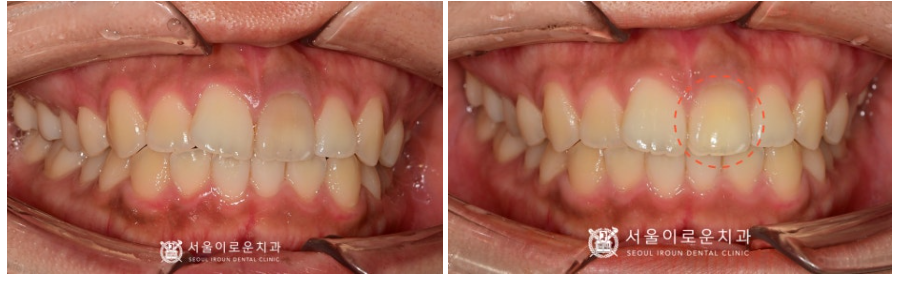

재신경치료 후

2회의 실활치미백이 마무리 된 모습으로,

변색이 눈에 띄게 많이 개선된 것을

확인하실 수 있습니다.

환.자분께서도 만.족해하시어

크라운 치료 없이 실활치 미백 후

레진으로 보강하여

치료를 마무리해 드렸답니다!

환.자분께서는 변색된 앞니가 개선되어

만.족해 하셨고,

특히 크라운 치.료를 염두에 두시고 오셨었는데

치.아삭제 없이 색상이 개선되어

만.족해 하셨습니다.

(2023.02.11ㅡ>2023.03.07)